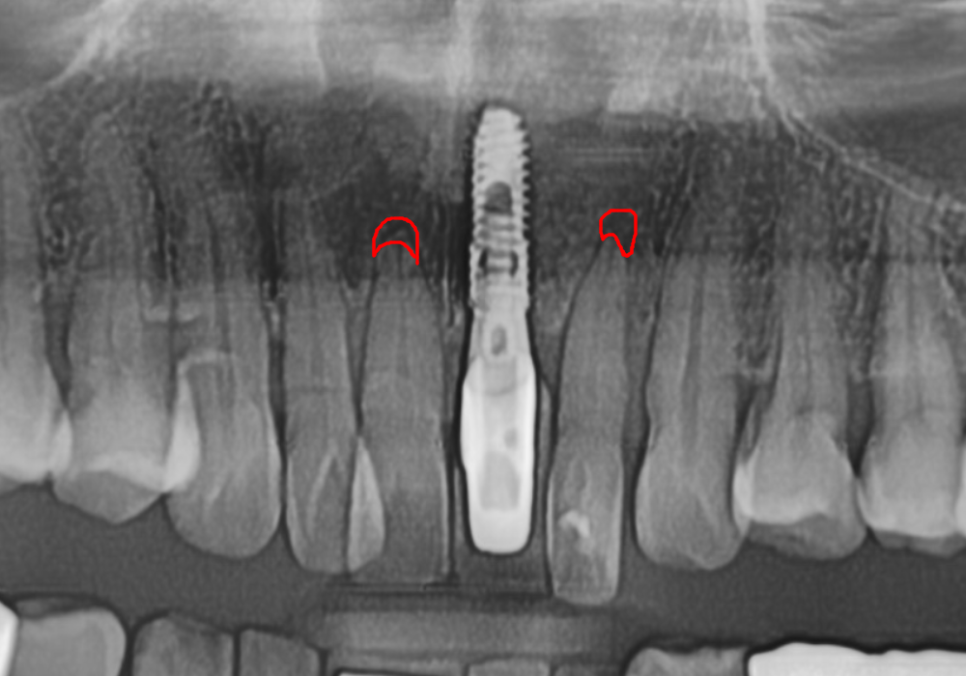

방사선 사진상,

치아 뿌리끝 염증도 진행되었고

뼈가 녹아 흔들림도 있던 상태라

231107 뿌리 끝 염증으로 뼈가 녹은 모습

방사선 사진상, 뿌리끝 염증으로

뼈가 녹은 부위가 있었고,

뼈 폭도 얇아 임플란트만 식립하기엔

무리가 있어 보였습니다.

231107